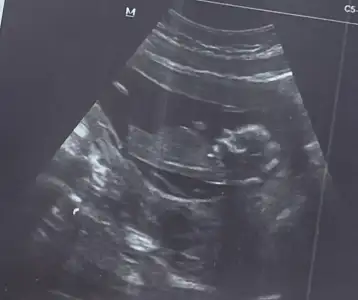

Kızlarım merhaba benim dee 13+2 cinsiyet tahmininizi alabilir miyimMaşallah bir kızımız daha geliyorsağlıkla kucağınıza alın inşallah

Adı üstünde tahmin öncelikli sağlık olsun ama bence erkekKızlarım merhaba benim dee 13+2 cinsiyet tahmininizi alabilir miyim![]()

Doktor tahminimce kız gibi duruyor dedi ama nasıl anlaşılıyor anlamıyorum. Sen nerden erkek kanısına vardın canımAdı üstünde tahmin öncelikli sağlık olsun ama bence erkek![]()

Ben kendi ultrason görüntümle karşılaştırdım benim kızımın böyle bir görüntüsü yok ondan erkek gibi geldi öğrenirsen muhakkak yaz bana çok merak ettimDoktor tahminimce kız gibi duruyor dedi ama nasıl anlaşılıyor anlamıyorum. Sen nerden erkek kanısına vardın canım![]()

Bence kız gibi duruyor sosyal medyada görmüştüm ne kadar doğru bilmiyorum karnı yuvarlak bebişin kızların öyle oluyorKızlarım merhaba benim dee 13+2 cinsiyet tahmininizi alabilir miyim![]()